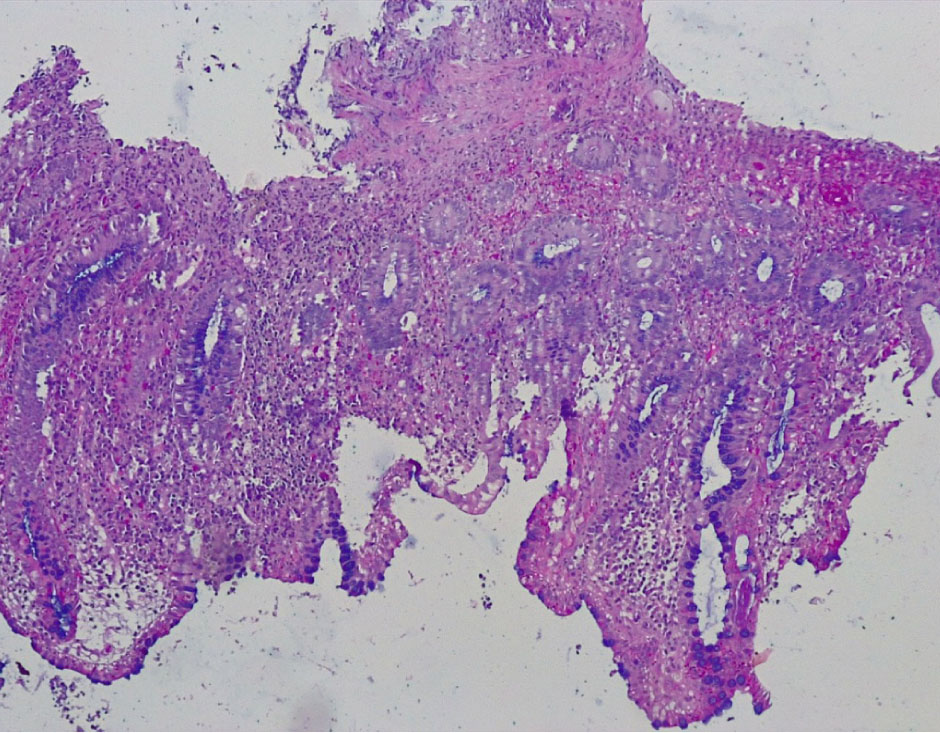

В контрольной группе биопсий слизистой оболочки (СО) толстой кишки, выполненной по поводу хронического поверхностного колита, были обнаружены следующие морфо-гистохимические изменения. СО толстой кишки была сохранена, цилиндрический (столбчатый) эпителий располагался в один слой, содержал на всем протяжении кислые гликопротеиды (ШИК-реакция). Крипты СО на всем протяжении были сформированы правильно, содержали до 12–15 бокаловидных клеток на крипту, содержали альциан+ муцин, что свидетельствовало о наличии в них нейтральных мукополисахаридов (рис. 1, 2).

Рис. 1. Контрольная группа: нормальное строение слизистой оболочки толстой кишки с сохранением цилиндрического эпителия и крипт, содержащих бокаловидные клетки. Окр. гематоксилин-эозином, ×100